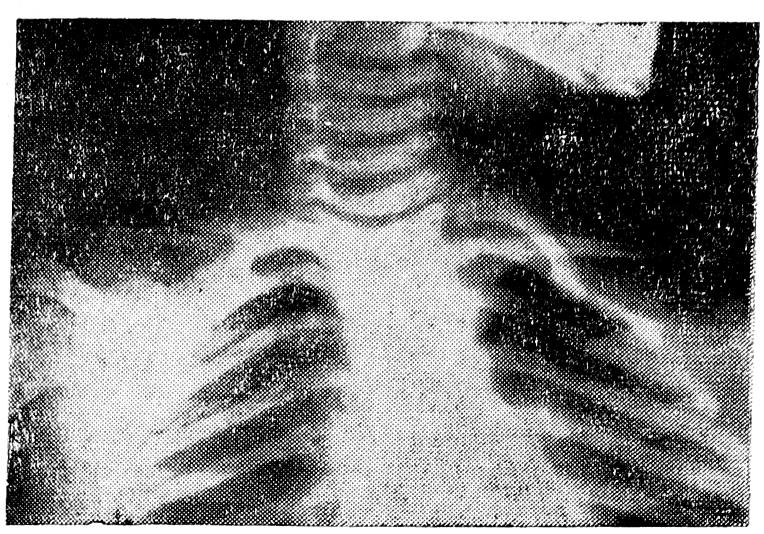

На рис. 3 представлена рентгенограмма плечевого пояса М. от 12/VІІ 1967 г. Правая ключица на отдельных участках на 1,5—2 мм толще левой, S-образный изгиб несколько круче. Расстояния от точки пересечения продолжения оси обеих ключиц с продольной осью позвоночника до акромиального конца ключицы, верхушки акромиального и клювовидного отростков, а также контура латерального квадранта головки плечевой кости с обеих сторон равны, хотя на первый взгляд рентгенограмма производит несколько иное впечатление.

Таким образом, наступила полная регенерация ключицы из надкостницы как вполне нормальное анатомическое образование, восстановилась функция плечевого пояса и верхней конечности.